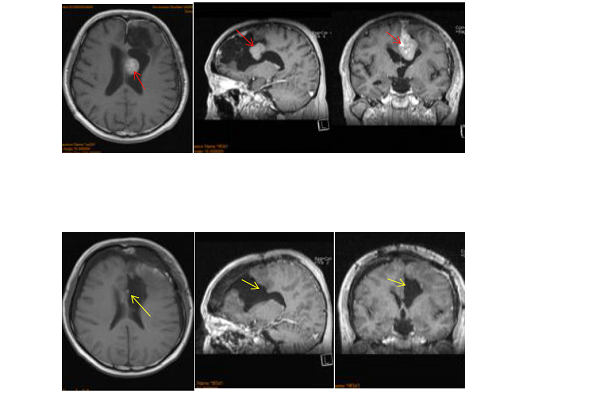

腦膜瘤前期癥狀

圖片來源文獻(xiàn)名:The Simpson grading revisited: aggressive surgery and its place in modern meningioma management (Kaplan-Meier estimates, both p < 0.001). The impact of the degree of resection increased with the WHO grade.